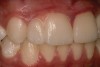

A 9-year-old girl, referred to a prosthodontic office by her pediatric dentist, presented with her mother’s chief complaint: “The kids are teasing her about her big front tooth.” Findings from radiographic and clinical examinations revealed fused maxillary central-peg lateral incisors, teeth Nos. 7 and 8, and a congenitally missing lateral incisor, tooth No. 10 (Figure 1 through Figure 3). An implant was selected as the ideal treatment to replace tooth No. 10 when somatic growth was complete. A diagnostic wax-up was fabricated to determine if the fused tooth could be made to resemble two teeth, using pink composite to give the illusion of an interproximal papilla. The patient was referred for an orthodontic consultation to plan for closure of the diastema between teeth Nos. 8 and 9 and achievement of proper alignment for implant No. 10. The patient was also referred to a periodontist for pretreatment assessment of the tooth No. 10 site. An endodontist was consulted should exposure of the large pulp occur during tooth preparation.

Fig 1 and Fig 2. Pretreatment photographs. Patient at 9 years of age on presentation.